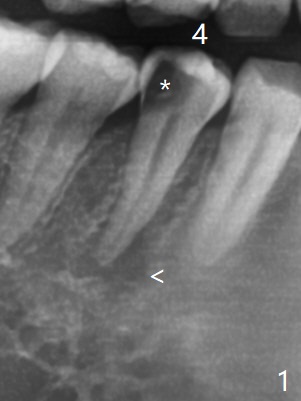

25岁硕士生,女,要求右下4补牙(图一:第一前磨牙),经过解释,欣然接受根管治疗。后者要领基本四条:无菌,根管笔直通畅,使用根尖定位仪和旋转式锥形扩大针和锥形牙胶尖。为了无菌,局麻后常规使用橡皮障(图二 *)。防止断针,尤其是旋转式锥形扩大针,根管治疗开口尽量大(图二箭头),保持扩大针笔直。开始根尖定位仪有点毛病,使用15号锉测定根管长度,不小心超越根尖大约3毫米(图三)。后来倒退4毫米,并得到根尖定位仪证实,主牙胶尖(30/.06)好像长度合适(图四),反复冲洗,最后再插入一个细牙胶尖一次性完成根管治疗和补牙(图五,六)。